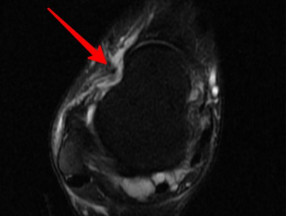

前方長骨刺

幾經(jīng)輾轉,李先生來到廣安醫(yī)院就診,骨科中心主任羅軍副主任中醫(yī)師為他進行了詳細專業(yè)的查體,結合影像檢查,診斷為右踝關節(jié)不穩(wěn)(距腓前及跟腓韌帶斷裂)、右踝關節(jié)創(chuàng)傷性關節(jié)炎。羅軍主任帶領大家詳細分析病情之后,決定為他施行踝關節(jié)鏡下病變組織清理和距腓前韌帶、跟腓韌帶重建術。

踝關節(jié)鏡見前方長骨刺

醫(yī)生們在手術中發(fā)現(xiàn),李先生的右踝關節(jié)軟骨損傷明顯,踝關節(jié)前方及內(nèi)外側均有不同程度的骨質(zhì)增生,相互撞擊引起疼痛,同時距腓前及跟腓韌帶斷裂。手術醫(yī)生利用磨鉆,小心翼翼將引起撞擊的骨刺一一去除,然后,修復了損傷的關節(jié)軟骨,最后,為他完成了距腓前和跟腓韌帶的修復。